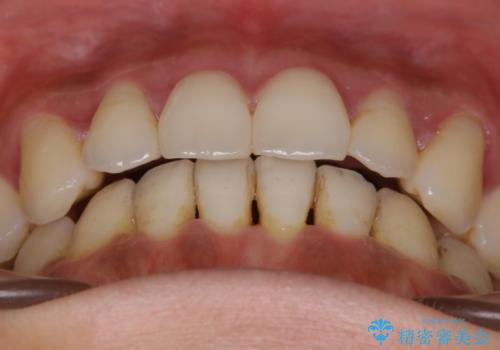

- 歯のガタつきによる見栄えや清掃困難を主訴にご来院されました。

左側の噛み合わせは上の歯が前方に寄ってきてしまっていることが原因のズレがありました。

ガタつき自体は歯列の幅の拡大やディスキング(IPR)でほとんど解消可能でしたが、噛み合わせのズレは歯の移動が必要だったため、左上にマイクロインプラントを使用し噛み合わせの改善とガタつきの解消を同時に進めるという方針をとりました。